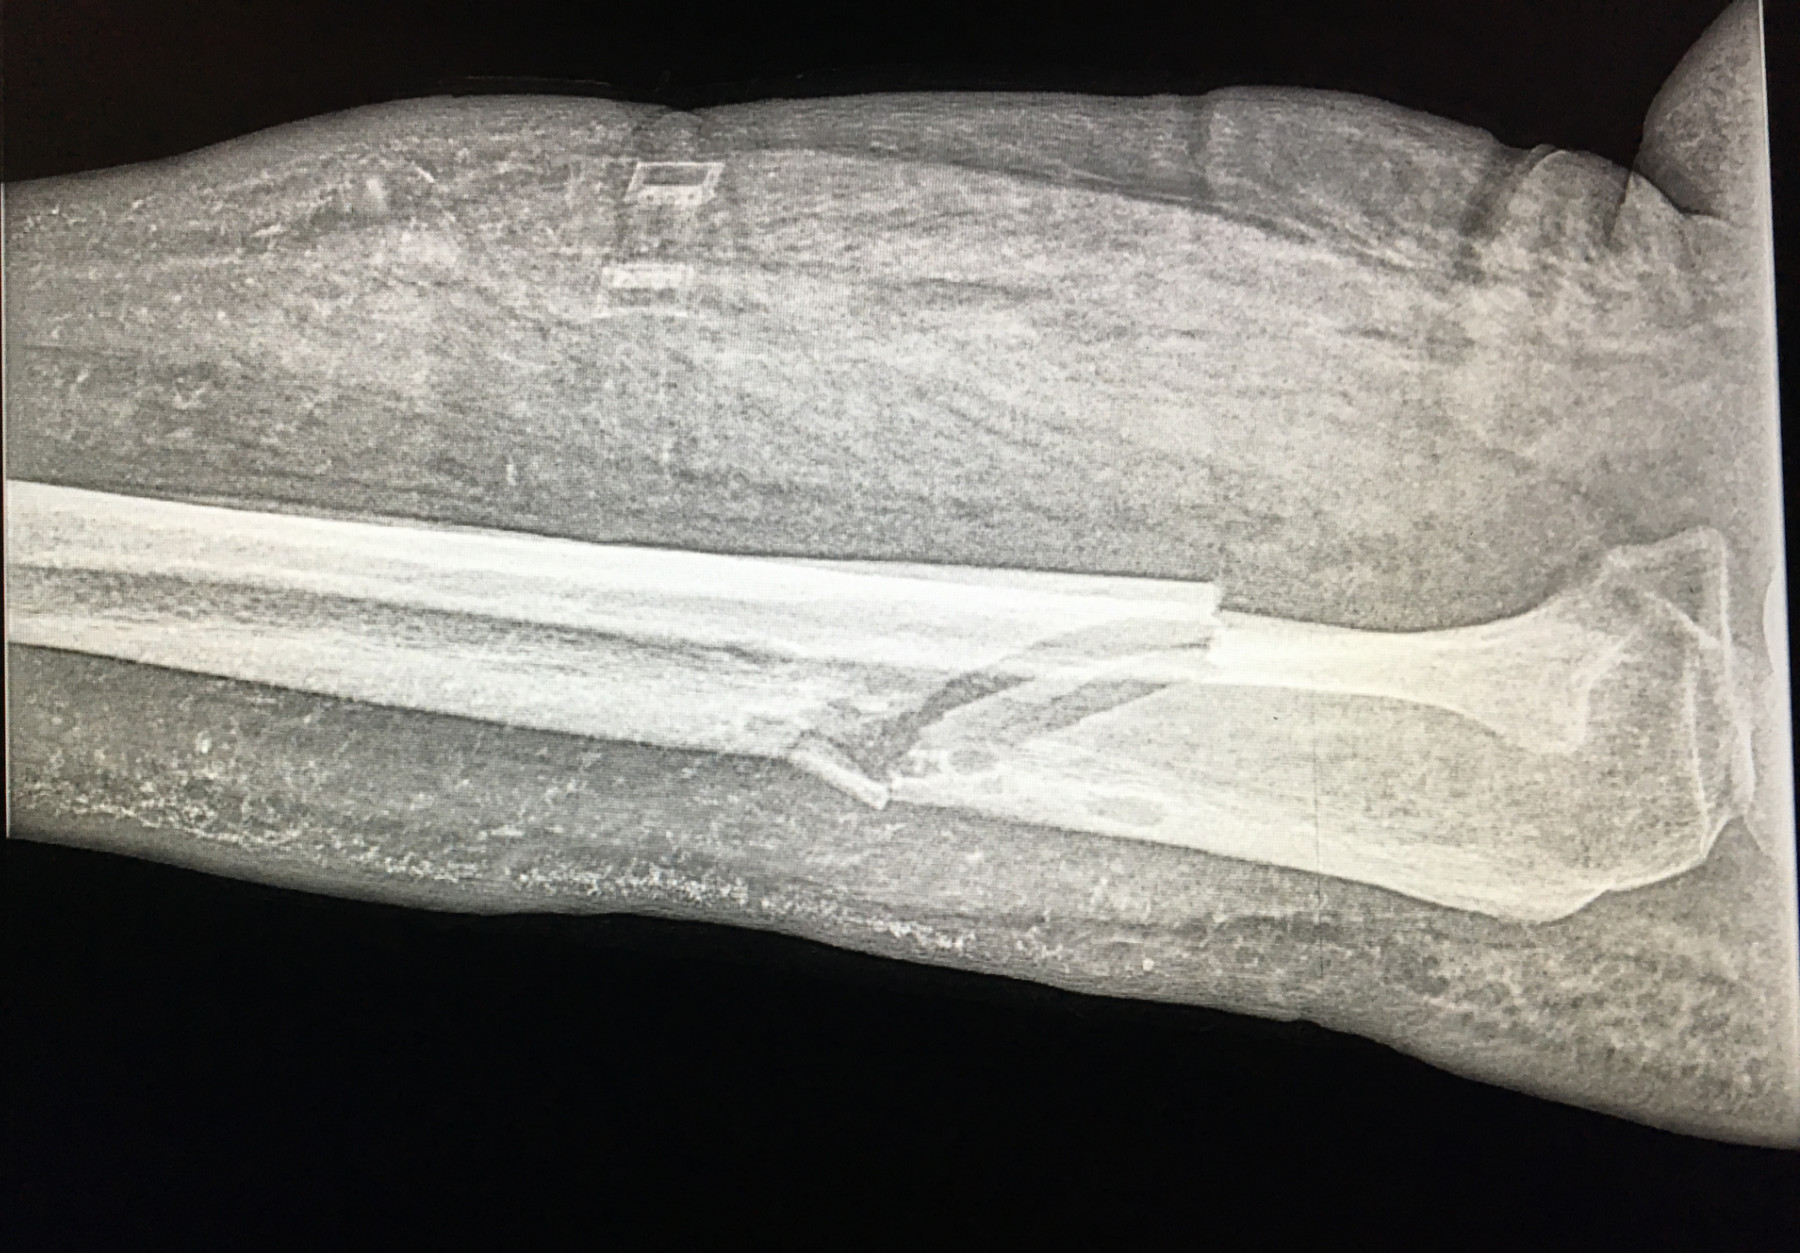

Cambios Térmicos en las Extremidades de Caballos,

Asociados a Golpes y su Evaluación por Termografía.

Los caballos de salto, en competencia, pueden derribar obstáculos y lastimarse. Si se golpean, no siempre claudican. Considerando al calor como un signo de inflamación, se evaluaron los cambios térmicos de 6 áreas de las extremidades torácicas y pelvianas de 23 caballos de salto en nivel de competencia de 1.05 a 1.60 m de altura, por medio de termografía durante 4 días de competencia (N=2208 áreas).